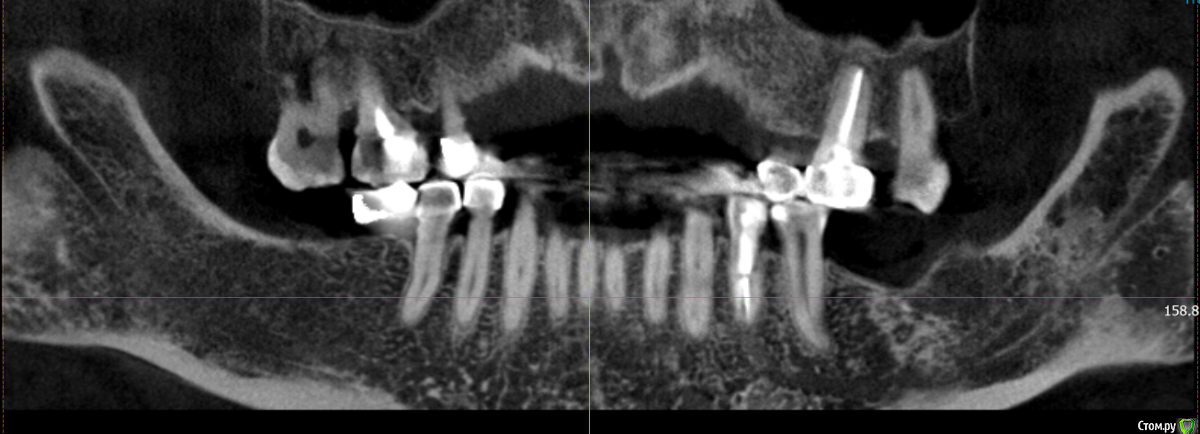

Dantist55 Опубликовано 22 декабря, 2014 Поделиться Опубликовано 22 декабря, 2014 Извиняюсь за фото, над фотопротоколом работаю. Критика приветствуется. 17 Ссылка на комментарий

Mane Опубликовано 22 декабря, 2014 Поделиться Опубликовано 22 декабря, 2014 в целом хорошо. но нет деталей где я смогу понять что качественно отработали: 1) кт срезы до и после с замерами чтоб было понятно на сколько нарастили 2)кт срезы с установленными имплантами чтоб было понятно какие болты удалось установить и стало чтоб всем понятно для чего наращивали - ведь вы растили в высоту и в ширину. 3) фото на этапе установленных имплантов - соотношение платформы импланта и уровня кости - заглубили или нет - если да то насколько. Ориентировались ли на будущий зенит зуба. мне понравилось. но чуйка что есть гиперлечение - думаю можно было болты и костную пластику совместить. Растить по высоте я скорее всего бы не стал. 1 Ссылка на комментарий

Dantist55 Опубликовано 22 декабря, 2014 Автор Поделиться Опубликовано 22 декабря, 2014 в целом хорошо. но нет деталей где я смогу понять что качественно отработали: 1) кт срезы до и после с замерами чтоб было понятно на сколько нарастили 2)кт срезы с установленными имплантами чтоб было понятно какие болты удалось установить и стало чтоб всем понятно для чего наращивали - ведь вы растили в высоту и в ширину. 3) фото на этапе установленных имплантов - соотношение платформы импланта и уровня кости - заглубили или нет - если да то насколько. Ориентировались ли на будущий зенит зуба. мне понравилось. но чуйка что есть гиперлечение - думаю можно было болты и костную пластику совместить. Растить по высоте я скорее всего бы не стал.КТ посмотрю позже на работе - я в отпуске.По высоте добавляли чтобы зубы не получились большими.Импланты не заглублял, т.к. у XIVE полированная фаска.Насчет гиперлечения может Вы и правы. Эту работу я сделал сразу после приезда от Кури. 2 Ссылка на комментарий